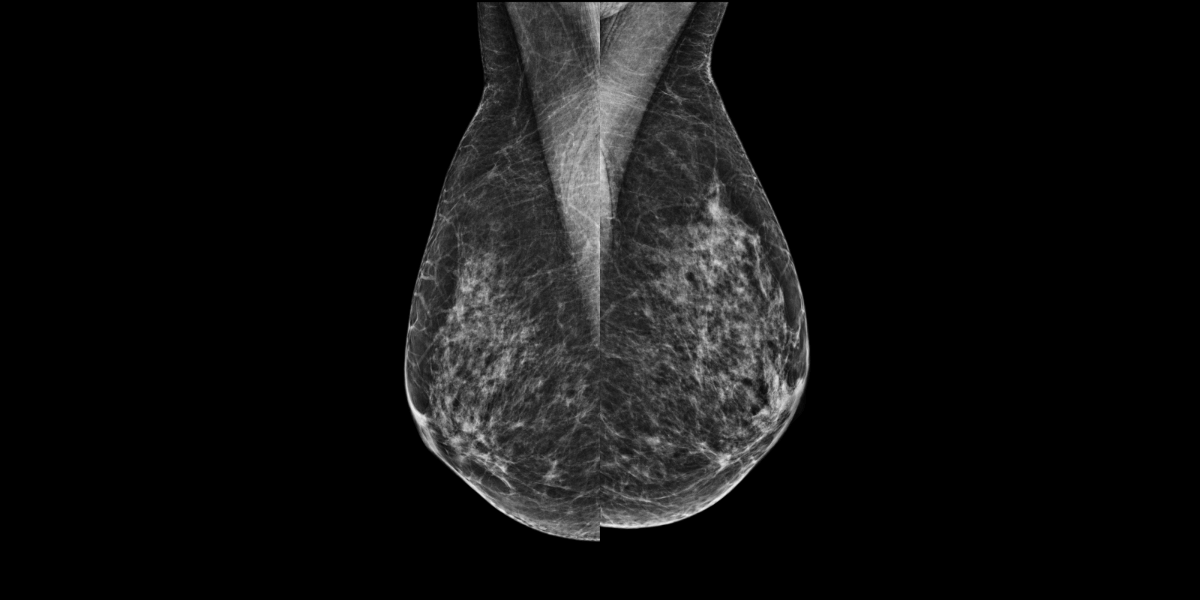

Femme de 65 ans, mammographie de dépistage.

Mammoscreen™ pointe une lésion du quadrant supéroexterne du sein gauche.

On note qu’en analyse rétrospective MammoScreen pointait déjà une lésion du QSE du sein gauche 2 ans auparavant mais classée peu suspecte.

Une échographie réalisée confirme une formation hypoéchogène sur le rayon de 1h00 à 4 cm du mamelon.

La biopsie réalisée confirme un carcinome lobulaire.